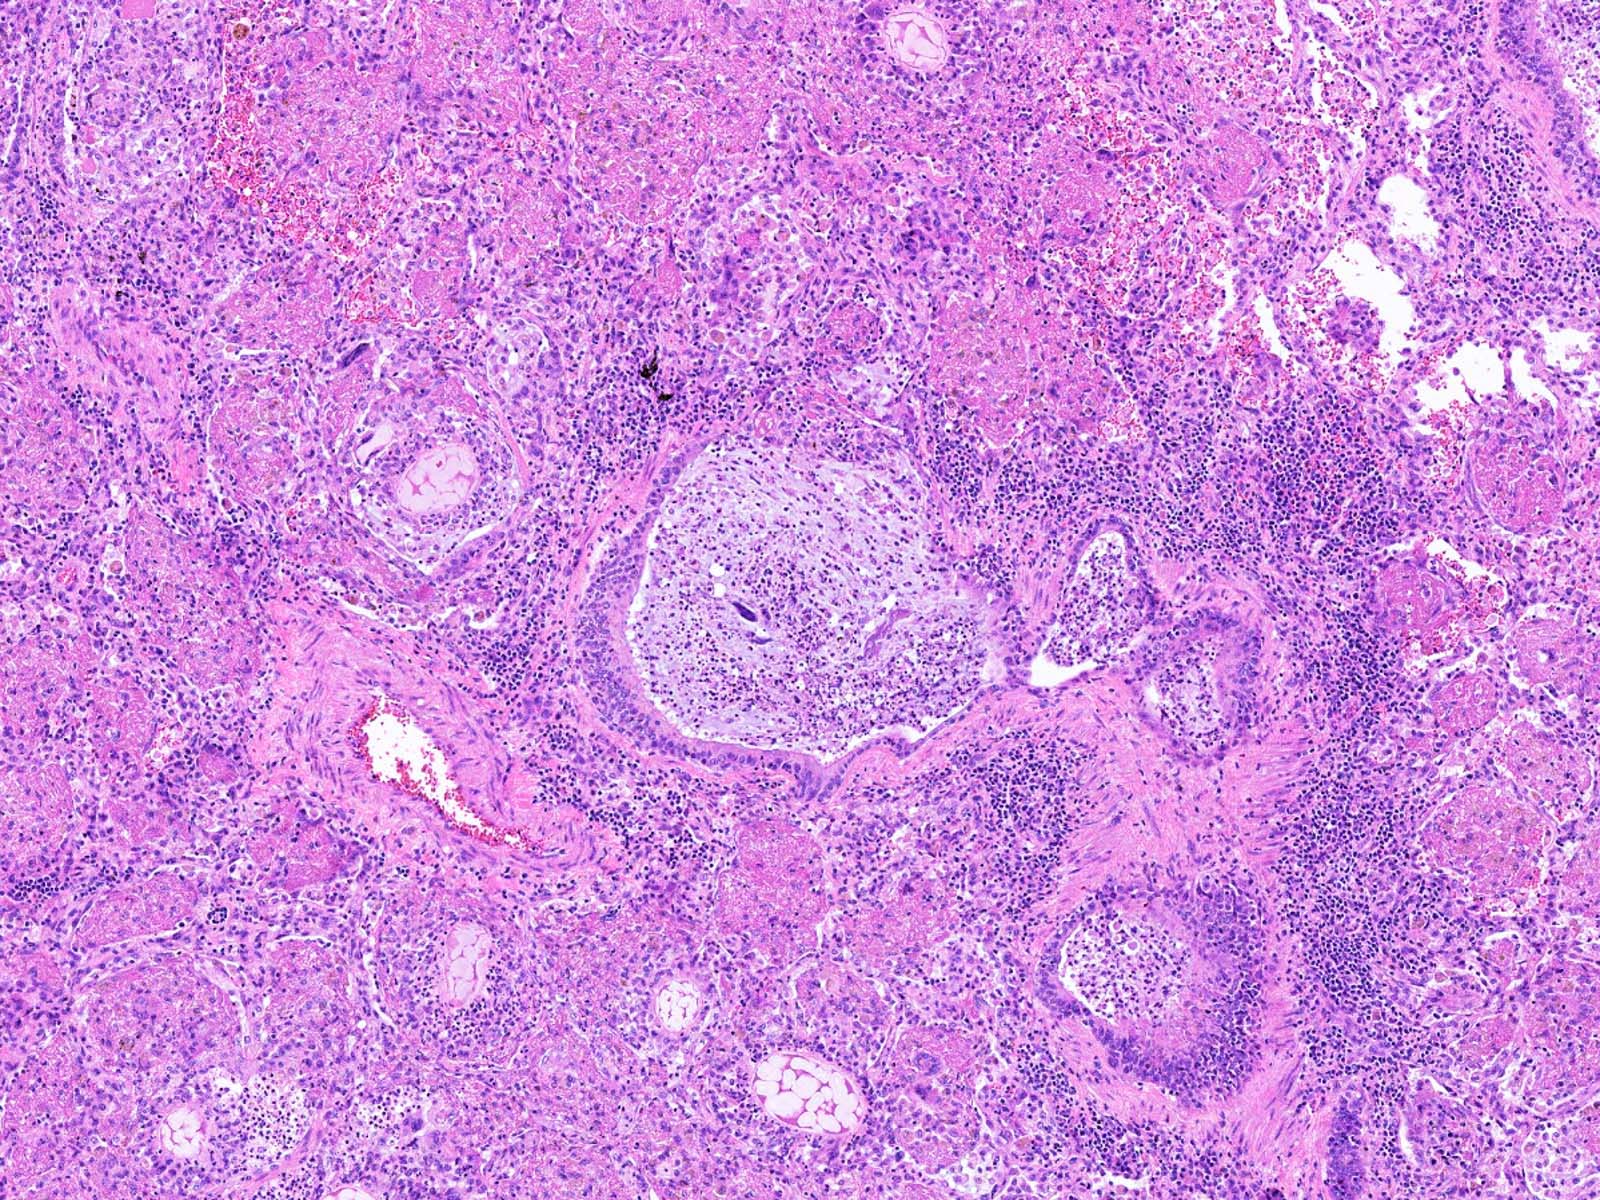

Microscopic (histologic) description

- Lobar pneumonia (Semin Diagn Pathol 2017;34:498):

- Uniform inflammatory infiltrate, the changes are at the same stage throughout the entire lobe

- Early stage: vascular engorgement, intra-alveolar fluid with few neutrophils and often bacterial colonies

- Massive confluent exudate with intra-alveolar neutrophils, red cells and fibrin, correlates with red hepatization on gross exam

- Progressive disintegration of red cells and the persistence of a fibrinosuppurative exudate, correlates with gray hepatization on gross exam

- Resolution phase: exudates converted to fibromyxoid masses rich in macrophages and fibroblasts

- Usually resolves with minimal fibrosis

- Pleuritis can be seen

- Bronchopneumonia:

- Most common pattern of pulmonary infection

- Different stages in the different areas

- Patchy intra-alveolar fibrinopurulent exudate with neutrophils

Microscopic (histologic) images

An 80 year old man presented with dyspnea, altered mental status and evidence of urinary tract infection. He was hospitalized in an intensive care unit for 2 weeks. The patient later developed fever, hypoxemia and new infiltrate on chest radiograph. An autopsy was performed and the lung showed the above histomorphology. What is the likely diagnosis?